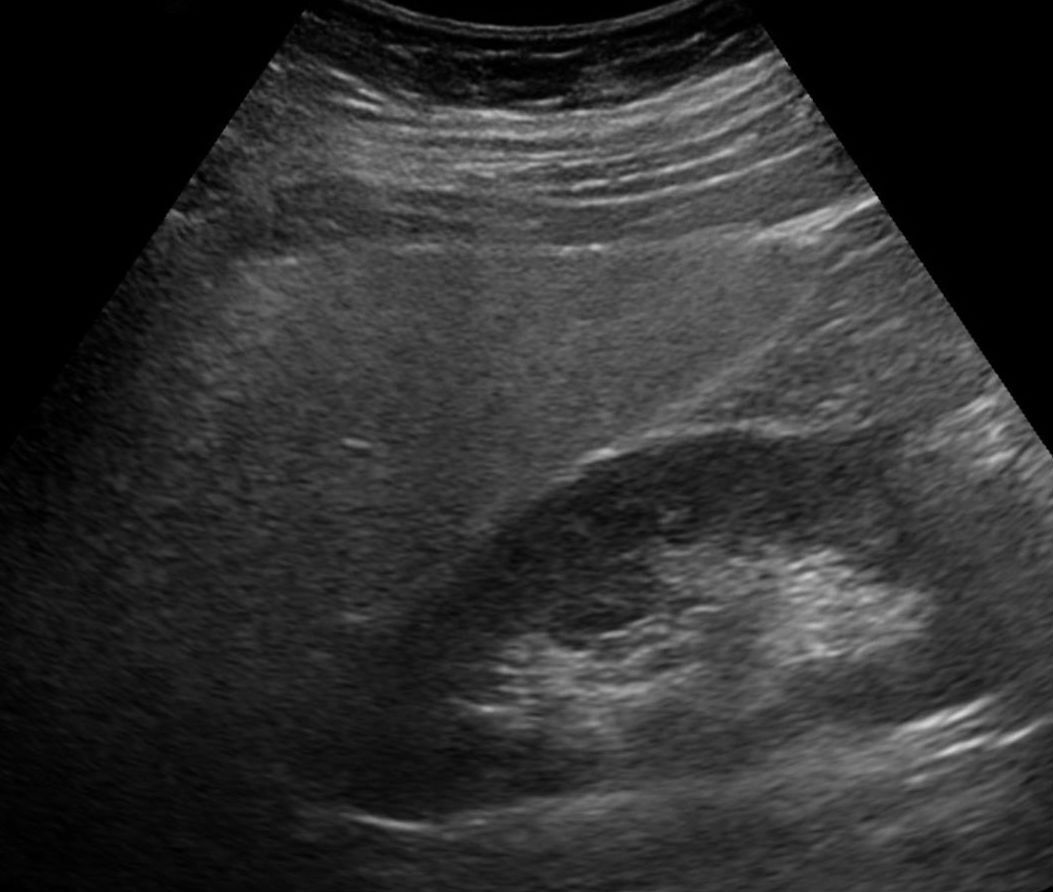

Im Ultraschall lässt sich eine Fettleber an ihrer höheren Echogenität erkennen – oft schon bevor Symptome auftreten. Im Ultraschall lässt sich eine Fettleber an ihrer höheren Echogenität erkennen – oft schon bevor Symptome auftreten. © wikimedia/Hellerhoff (CC BY-SA 3.0)